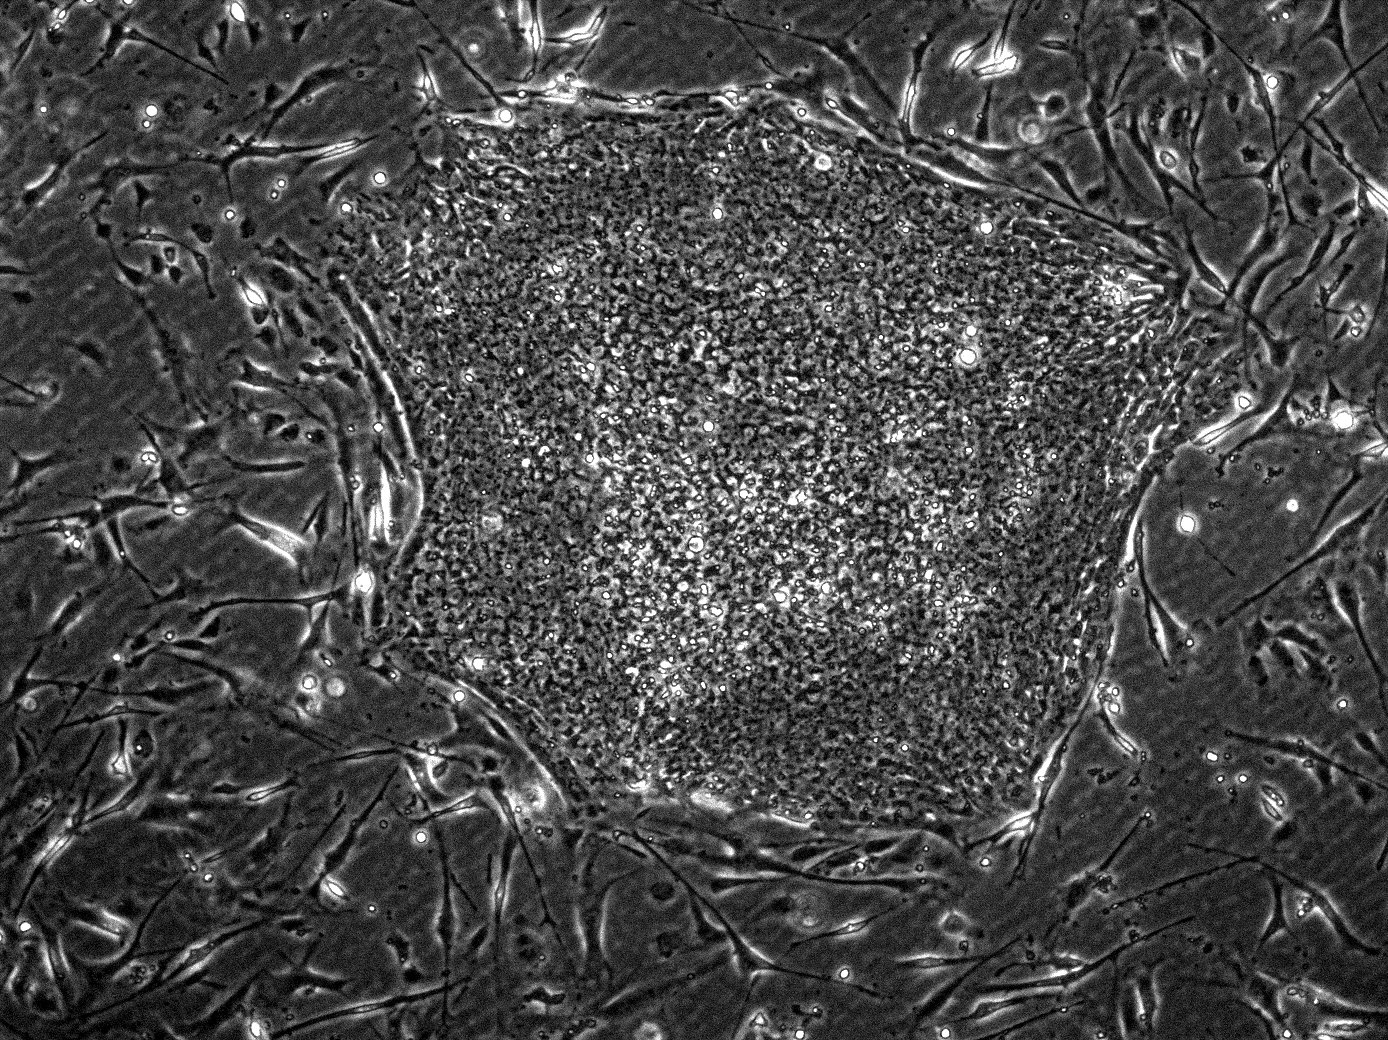

Scientists from UC San Francisco and Cedars-Sinai have developed a new way to prompt stem cells to form specific organs by programming a few “organizer” cells to coax other stem cells into forming rudimentary, organ-like structures. Think of it like having a construction foreman who knows exactly how to direct a team of workers to build something they’ve never built before.

The research team showed that these organizer cells can create structures that contract like a beating heart and have cavities resembling heart ventricles, with some structures growing fine appendages resembling blood vessels. What makes this breakthrough so remarkable is that researchers essentially wrote their own simple developmental programs from scratch, which they believe could lead to more effective ways to repair and regenerate the body.

Lab-Grown Mini-Organs Are Teaching Us How Bodies Really Work

Organoid studies have verified that nearly all organs can be generated in the form of a mini-organ by recapitulating embryonic body patterning and establishing an organ-forming field among self-organizing pluripotent stem cells. These miniature organs aren’t just scientific curiosities – they’re becoming powerful tools for understanding disease and testing treatments.

Organoid technologies can currently only regenerate mini-organs with limited structural and functional recovery, but this technique could be applied as an assay system for drug discovery and as a means to cure damaged organs by transplanting multiple mini-organs and organ systems. Imagine having a tiny version of your liver or kidney that doctors could test different medications on before treating you.